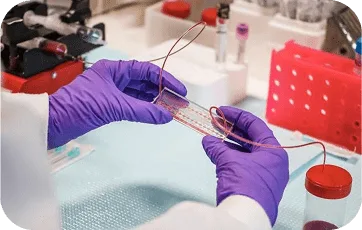

Especialista em Cirurgia Robótica

Tecnologia de ponta com melhores resultados e recuperação